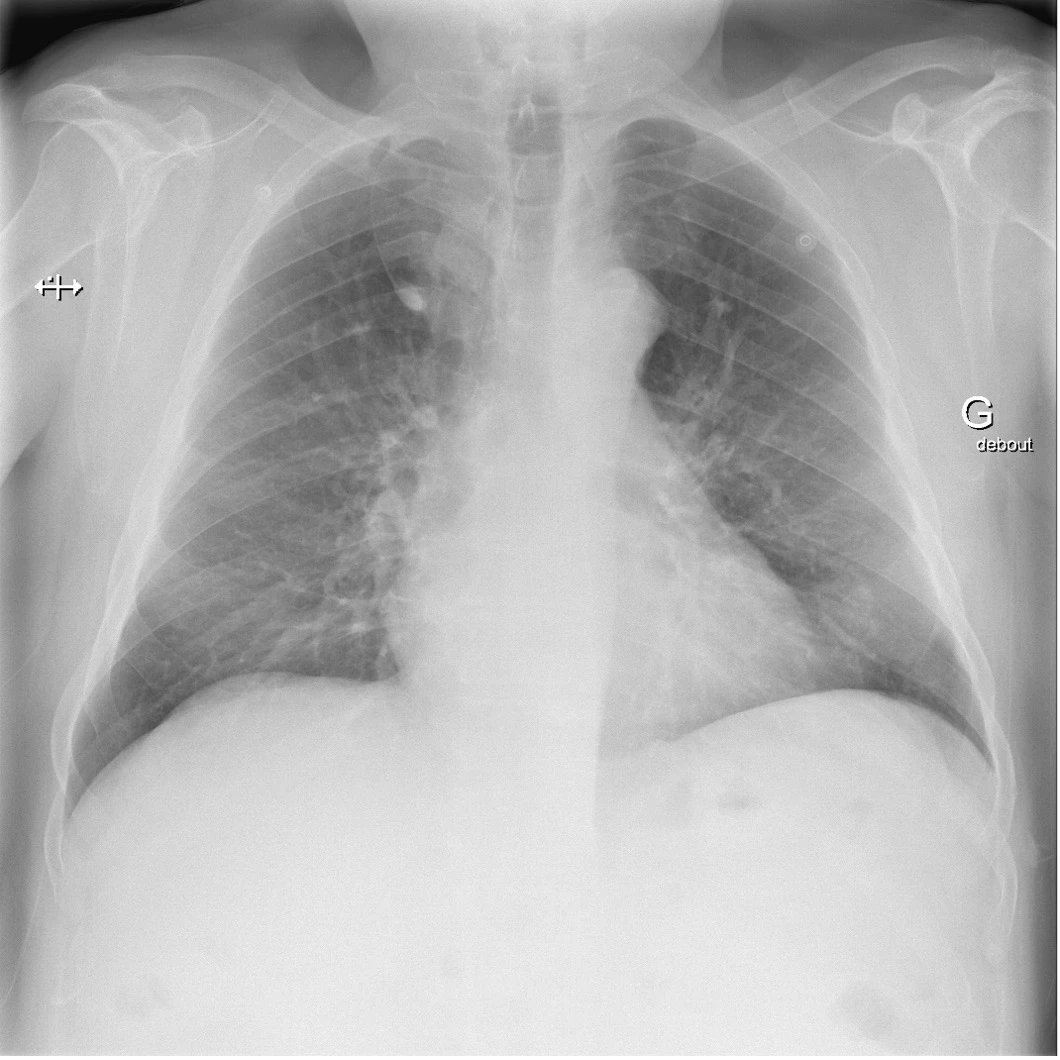

Masse dans le lobe supérieur droit

Le lobe azygos est une anomalie congénitale, ou variante anatomique. Bien que rare (il se retrouve chez environ 1% de la population avec un ratio homme : femme de 2 : 1 et sur 0.4 % des radiographies thoraciques), cette variante doit être connue de la ou du clinicien·ne car elle peut être confondue avec un néoplasie pulmonaire, un abcès ou une bulle d’emphysème voir un pneumothorax.

Ce « lobe accessoire » est formé durant l’embryogenèse, par la migration anormale d’une veine précurseur de la veine azygos, dans le segment apical du lobe pulmonaire supérieur droit (beaucoup plus rarement à gauche), au lieu d’une migration dans le médiastin. Cette indentation du lobe supérieur forme le lobe azygos qui lui est adjacent. Le lobe azygos n’est pas à proprement parlé un lobe, mais bien une partie du lobe supérieure. Il n’est pas vascularisé ou ventilé par un système indépendant ou spécifique.